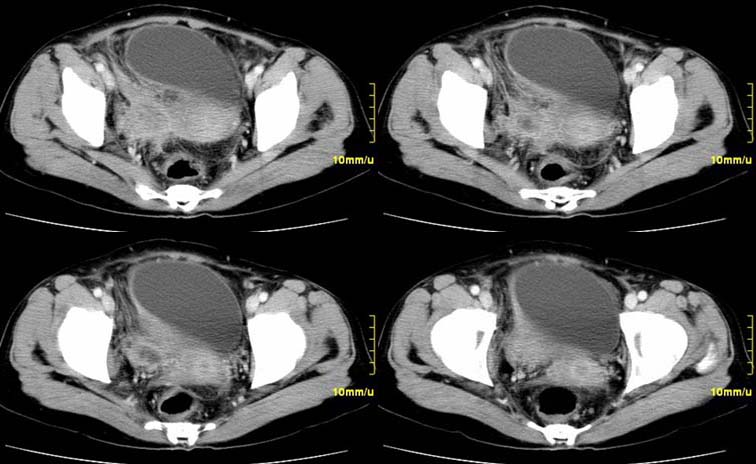

患者,52,右下腹疼痛一月,当时有发热,抗炎治疗20余天,至今仍疼痛,且有低热。

增强

右附件区软组织包块,内囊变坏死,边缘模糊,与子宫,与膀胱分界不清,增强强化与子宫密度相近.盆腔内无肿大淋巴结考虑炎性包块可能性大。

右附件区软组织包块,内可见坏死,边界不清,周围软组织及脂肪组织可见密度增高,膀胱右侧壁增厚,并且呈膨胀不全的改变,考虑炎性包裹,不知道有没有手术史??

临床特点:

右下腹疼痛一月,当时有发热,抗炎治疗20余天,至今仍疼痛,且有低热,具有典型炎症的临床表现。

ct表现:

右侧附件见一肿块,边缘与周围组织分界不清,增强扫描见肿块明显强化,越到后期强化越明显,中央见坏死,内壁光整,与临近子宫壁、直肠及膀胱后壁均见炎症波及。这种厚壁肿块、内缘光整外缘模糊、增强扫描强化越后越强是附件脓肿典型的ct表现。

诊断:

右侧卵巢输卵管慢性脓肿,炎症波及临近子宫、直肠及膀胱形成粘连。